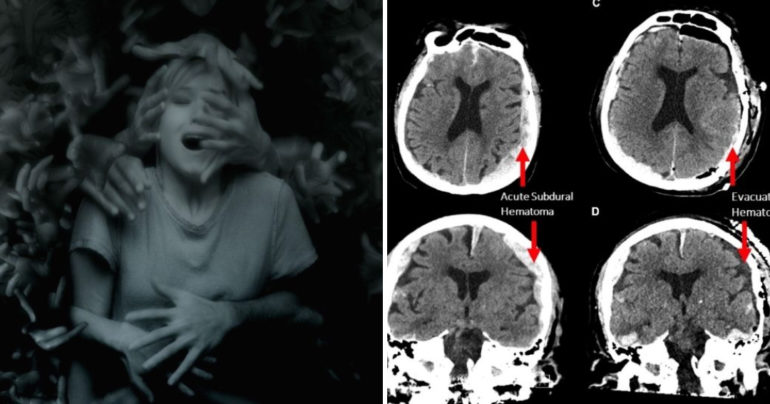

Americkí vedci skúmali zariadením EEG mozog 87-ročného muža, ktorý trpel epilepsiou a podarilo sa im zaznamenať jeho mozgové vlny 15 minút po tom, ako umrel na infarkt. Vedci veria, že zvýšenie počtu mozgových vĺn, známych ako „gama oscilácie“, u tohto pacienta je dôkazom podporujúcim myšlienku, že tesne pred a po smrti sa človeku „pred očami prehráva celý jeho život“.

„Prostredníctvom generovania oscilácií, ktoré sa podieľajú na obnovovaní pamäte, môže mozog prehrávať tesne pred smrťou človeka dôležité životné momenty, podobne ako tie, ktoré boli zaznamená pri zážitkoch hraničiacich so smrťou,“ uviedol podľa webu LAD Bible doktor Ajmal Zemmar, hlavný autor štúdie.

Podľa neho a jeho kolegov to môže byť dôkazom, že umierajúcemu človeku sa tesne pred smrťou alebo pri hraničných momentoch, ktoré môžu k smrti viesť, ale tá napokon nenastane, pred očami akoby „prehrával jeho celý život“. Podobné zážitky už totiž opísali mnohí svedkovia, ktorí sa k smrti priblížili, no napokon sa ich podarilo zachrániť.

Výsledky štúdie na 87-ročnom pacientovi, ktorý umrel na infarkt, tiež podporujú aj výskumy vykonané na potkanoch. Podobné zmeny v mozgových vlnách sa totiž podarilo zachytiť aj u týchto tvorov. Prípad muža bol však prvým zdokumentovaným u človeka. Súčasný výskum tak naráža na dve prekážky. Prvou je tá, že ide o prvý takýto prípad a bude teda potrebné zdokumentovať u ľudí aj ďalšie im podobné. Druhou je tá, že mozog skúmaného pacienta už bol poškodený predchádzajúcimi epileptickými záchvatmi.

Odborníci tak nedokážu jednoznačne dospieť k záveru, či sa podobné veci dejú aj v mozgu iného človeka v čase jeho smrti.

Z tohto výskumu sa ale podľa vedcov môžeme naučiť jednu dôležitú veci. „Hoci majú naši blízki už zatvorené oči a sú pripravení odísť na onen svet, ich mozgy si zrejme prehrávajú niektoré z najkrajších momentov, ktoré vo svojom živote zažili,“ dodal Zemmar.